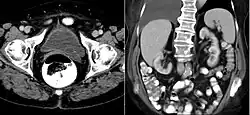

A ureterocele is a congenital abnormality found in the ureter. In this condition the distal ureter balloons at its opening into the bladder, forming a sac-like pouch. It is most often associated with a duplicated collection system, where two ureters drain their respective kidney instead of one. Simple ureterocele, where the condition involves only a single ureter, represents only twenty percent of cases.

Since the advent of the ultrasound, most ureteroceles are diagnosed prenatally. The pediatric and adult conditions are often found incidentally, i.e., through diagnostic imaging performed for unrelated reasons.

IVU-shows Adder head appearance or Cobra head appearance. Cystoscopy-shows translucent cyst which is thin walled surrounding ureteric orifice